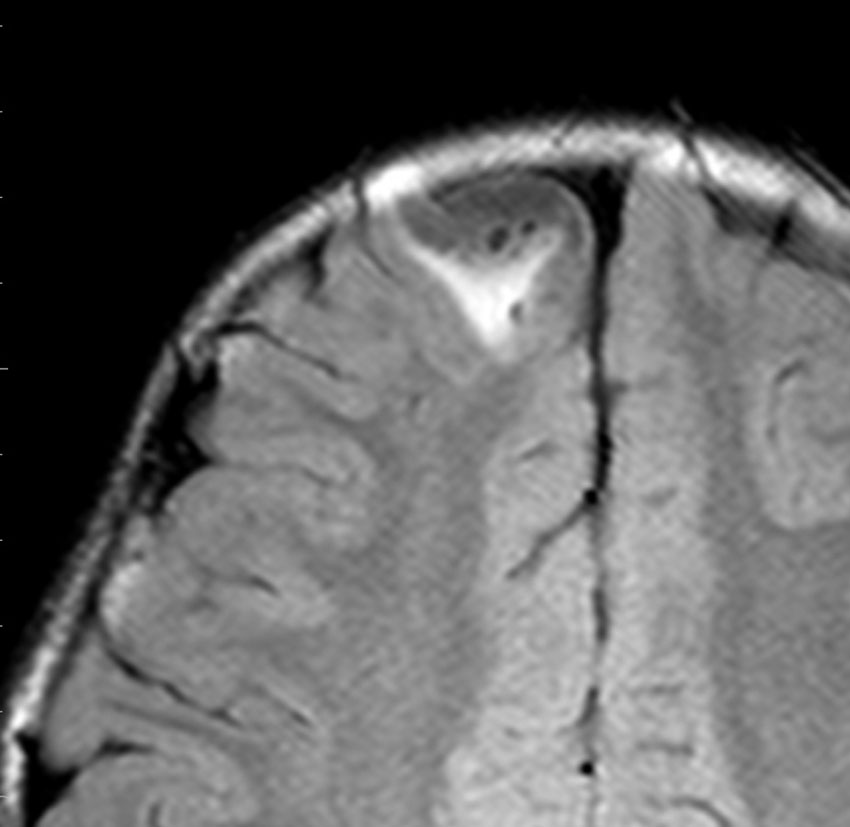

画像診断

- とても難しいといえます,特徴的な所見がないからです

- ほとんどが髄膜に接する脳表を巻き込む病変なのです

- 小さな多房性のう胞を伴ったり,脳内に結節とのう胞を形成するものもあります

- T1強調では等信号から低信号

- T2強調画像では低信号領域と血管のflow-voidがみられます

- ガドリニウム増強では不規則な増強像を見ることが多いです

- T2低信号の部分(結節)が強くガドリニウム増強されることも特徴かもしれません

難治性てんかんで発症した小児ですが,どう見てもDNTなのかなと思います。石灰化もありません。一般的に,meningioangiomatosisの術前診断は困難であると言えます。いずれにしても治療はlesionectomyです。